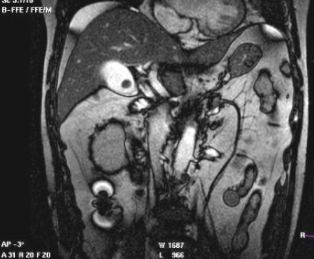

CT的密度分辨率高,更有利于胆结石的发现。胆石的CT表现与其化学成分密切相关,其CT值与胆固醇含量呈负相关,与胆红素和钙含量呈正相关。

CT表现主要有:高密度结石(均匀或不均匀);略高密度结石;等密度结石,与胆汁密度相等平扫不易区分;低密度结石;环状结石。